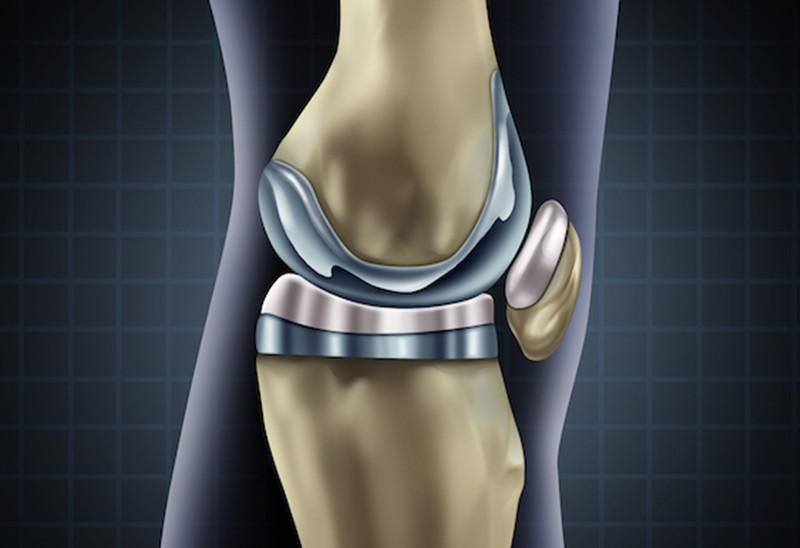

这个结果说明人工膝关节比想象的使用时间要长,并且大部分患者没有感到不适。但也必须承认调查的范围比较小,只有128名患者,还需要更多的数据支撑。二次翻修手术主要是人工关节的使用寿命造成的,它主要包括以下几个原因:

- 患者年龄: 年轻患者的自然寿命更长,而且活动量也大,因此50岁左右的患者,更可能需要二次重新安装人工膝关节。

- 患者活动: 有些活动可能不适合膝关节置换患者,比如高强度有氧运动,跑步,跳跃,举重,以及各类球类运动。不是患者不能进行这些运动,而是会对人工关节施加过大的压力,加速磨损。

- 患者体重: 身材越肥胖,人工膝关节承受的重量越大,行走时膝盖承受的重量是体重的2-3倍,上下楼梯则达到5-8倍,肥胖会造成人工关节负担过重,也会加速磨损。因此置换后保持健康的体重很重要。